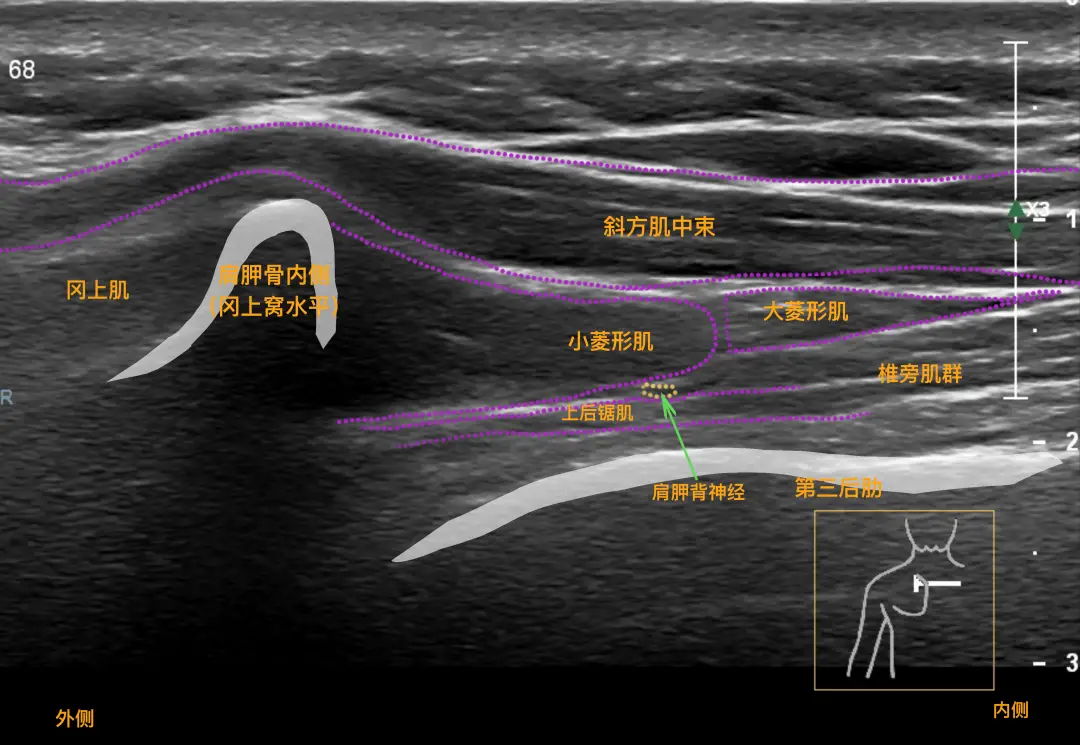

肌骨超声,一般是指肌骨关节系统超声检查规范;对肌肉、骨骼、关节及关节辅助结构和邻近软组织,包括韧带、肌腱、滑囊、滑膜、神经、软骨等。彩超检查,是很普遍、使用率很高的影像学检查方法之一;其用的范围很广,准确率普遍特别高,而且检查时间很短。那么,肌骨超声与彩超的区别有哪些?接下来就给大家解答这个问题。

1、肌骨超声,实际上就是用彩超来检查肌肉、骨骼、外周神经这些病变;唯一的要求就是浅表探头的分辨率要高一些。因为看的基本上都是比较表浅的组织,要求分辨率高、层次清晰,尤其微小血流这个要求也要高一些。就像是肌腱,肌腱本身是非常少的血流信号,正常情况下是看不到它有血流的;但是,它一旦有了病变的时候就会有血流,就会有非常微小的血管增生,但这个血管它里面的血流速度非常的慢。 2、常规的这些探头,可能会探测不到这部分血流信号,但是这部分血流信号对诊断肌腱炎的时候非常有帮助,可以提供一个依据。所以,就是对浅表探头它的要求比较高;浅表的分辨率,浅表的血流信号显示这方面,其它的彩超探头没有这个优势。实际上,超声设备是一样的,就是更多用的一个浅表的探头,要求浅表探头的分辨率。最重要的就是把超声用于以前的心脏、腹部、妇产方面的一个检查手段,用到了肌肉、骨骼、神经这些方面的检查。